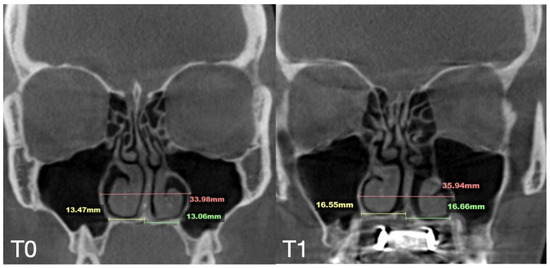

2.7. Case D: Midfacial Asymmetry Correction with Guided Expansion

| Case D | 26.25 | 33.27 | 31.54 | 55.9 | 61.84 | 60.37 | 33.98 | 35.94 | 38.09 | 29.77 | 29.24 | 29.02 | 6.2 |